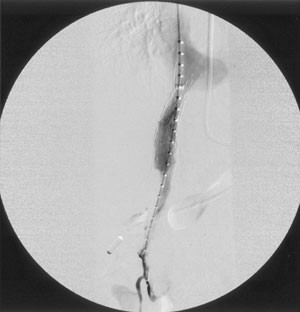

Percutaneous Stent Placement as Treatment of Renal Vein Obstruction Due to Inferior Vena Caval Thrombosis

A patient who had undergone his third orthotopic liver transplantation nearly 9 years prior to presentation developed worsening hepatic and renal function, as well as severe bilateral lower extremity edema. Magnetic resonance imaging demonstrated vena caval thrombosis from the suprahepatic venous anastomosis to the infrarenal inferior vena cava, obstructing the renal veins. This was treated by percutaneous placement of metallic stents from the renal veins to the right atrium. At 16 months clinical follow-up, the patient continues to do well.

Figure 1